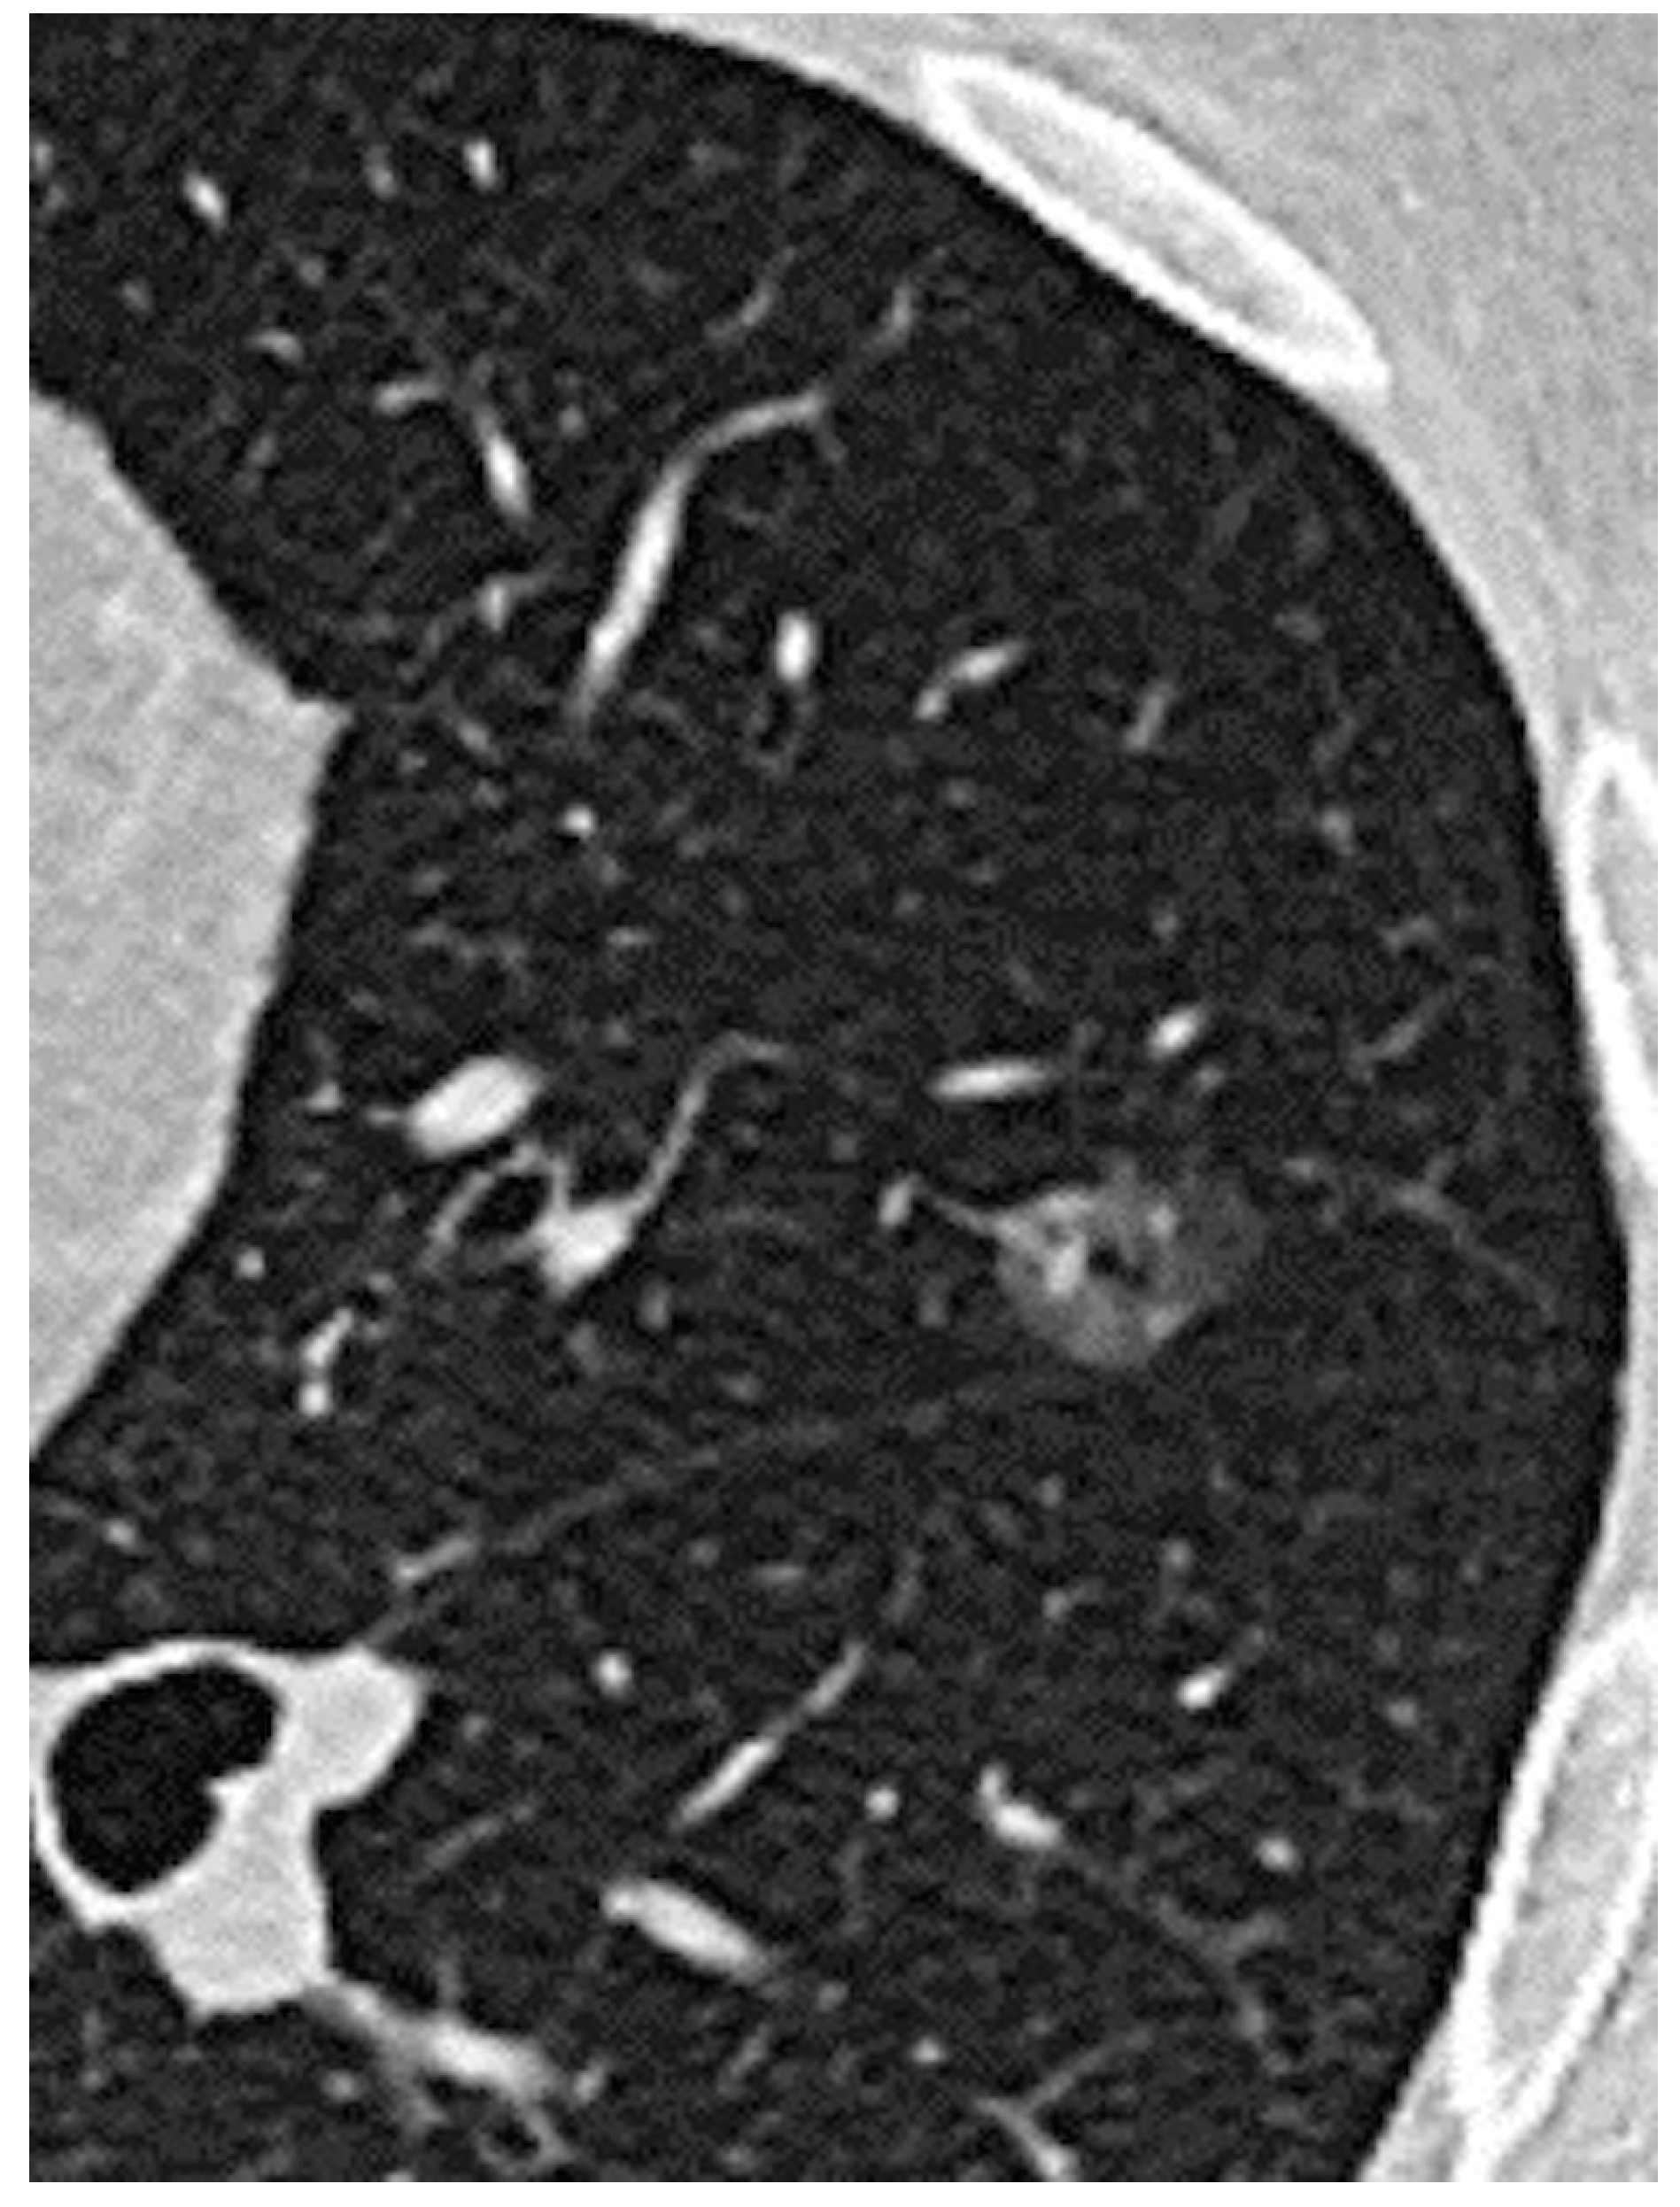

| Pure GGO, n (%) | 162 (42%) | 108 (67%) | 54 (24%) | <0.0001 |

| Pure GGO | 3.3 | 2.9–4.5 | 0.01 |

| Pure GGO | 2.3 | 2.8–4.8 | 0.003 |